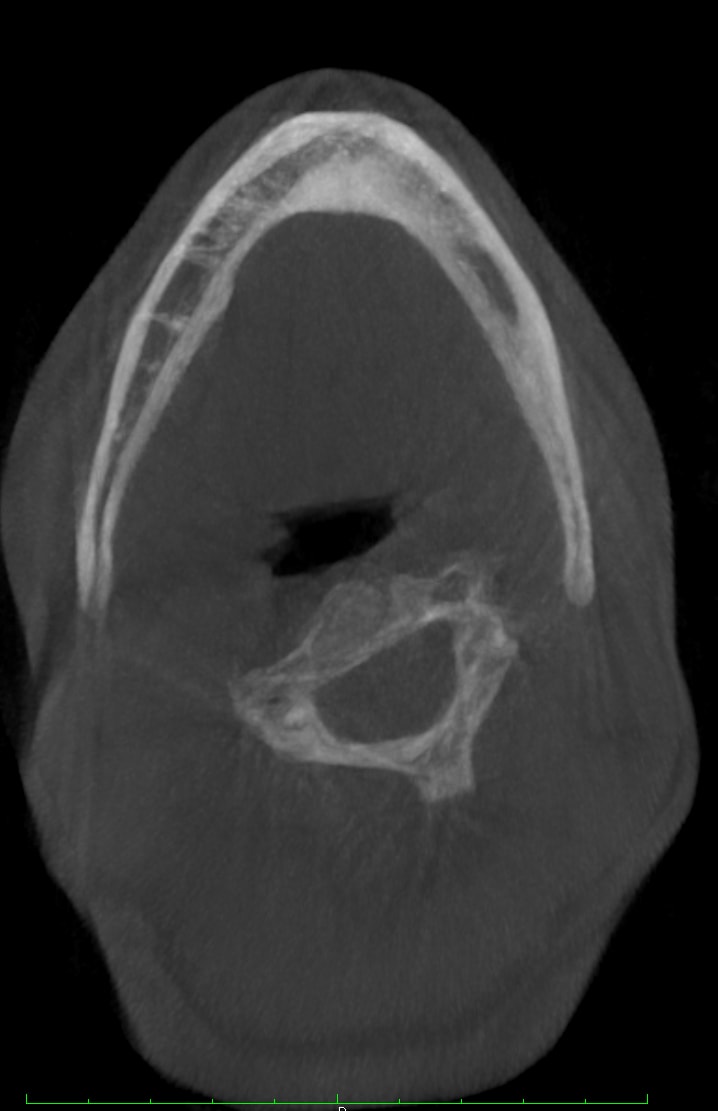

1. Many have advocated that the use of 3D imaging is certainly useful in treating patients with impacted maxillary canines. This is certainly true. However, only 1 to 2 percent of the population has impacted canines. The population of most orthodontic practices is published that 5 percent of the practice’s patients seeking treatment have impacted canines. If this is the main reason for taking DICOM images on patients, then these images should be outsourced. The cost of purchasing a 3D machine for 5 percent of the office’s patients does not make financial sense. A 2-dimensional pan or ceph does not adequately image the impacted teeth for not only surgical planning but also the mechanics needed to move these teeth into alignment. It has been reported that 62% of palatally impacted canines are touching the roots of laterals and centrals. This is information that 3D imaging illustrates. This could often change the mechanics needed to properly position the canines without damaging the roots of adjacent teeth. However, the 3D imaging of impacted teeth certainly is advantageous to the orthodontist or oral surgeon that will surgically expose the non-erupted teeth. This is illustrated in Figure 1 through Figure 3. One can readily see the benefits to the patient for using 3D imaging technology for the treatment of impacted teeth.